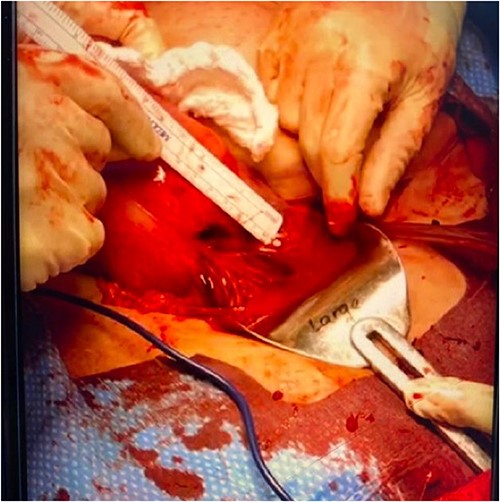

Upon abdominal entry, hemoperitoneum was identified and 200 mL of blood was evacuated. Both fetuses were noted to be free-floating in the abdomen (Fig. 2). A 2-cm uterine rupture was identified likely along the prior hysterotomy site (Fig. 3). An ~3 × 3 cm non-expanding hematoma was noted just under the serosa in the midline of the lower uterine body. The placental tissue and clots within the uterus were removed with sharp curettage through the 2-cm uterine rupture site. The hysterotomy was then closed with 2-0 Vicryl in a running-locked fashion. The fascia, subcutaneous tissues, and skin were closed in standard fashion.

Fetus A (left) with grossly normal phenotype with attachment to the placenta. Fetus B (right) with grossly normal phenotype and intact amniotic membranes.